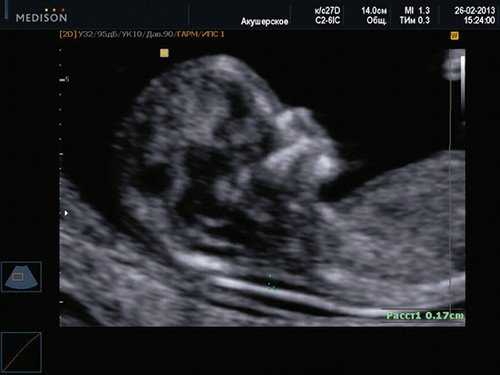

Копчико-теменной размер плода (КТР) для проведения скрининга I триместра должен быть в пределах 45-84 мм. Для оценки носовой кости в I триместре беременности необходимо соблюдать строгие условия. Это адекватное увеличение (на снимке должны быть только голова и верхняя часть грудной клетки), среднесагиттальный скан (должны быть визуализированы эхогенный кончик носа, небный отросток верхней челюсти, диэнцефалон), нос представлен тремя "К" (кончик носа, кожа, кость). Кожные покровы и кости носа визуализируются в виде знака "равенства", нос параллелен датчику.

Если все критерии соблюдены, то на уровне носа плода должны быть видны три четко различимые линии: верхняя линия представляет собой кожу, книзу от нее визуализируется более толстая и более эхогенная, чем кожа носовая кость. Третья линия, визуализируемая кпереди от носовой кости и на более высоком уровне, чем кожа - это кончик носа (рис. 1).

Рис. 1. Нормальная носовая кость.

Считается, что носовая кость нормальна, когда она по своей структуре более эхогенна, чем надлежащая кожа и патологична, если она не видна (аплазия) (рис. 2) или ее длина меньше нормы (гипоплазия) (рис. 3). В случае одинаковой или меньшей эхогенности носовой кости чем кожи носовая кость считается патологической (рис. 4).

а) Стрелкой указана эхогенная кожа плода.

б) Стрелкой указано отсутствие носовой кости.